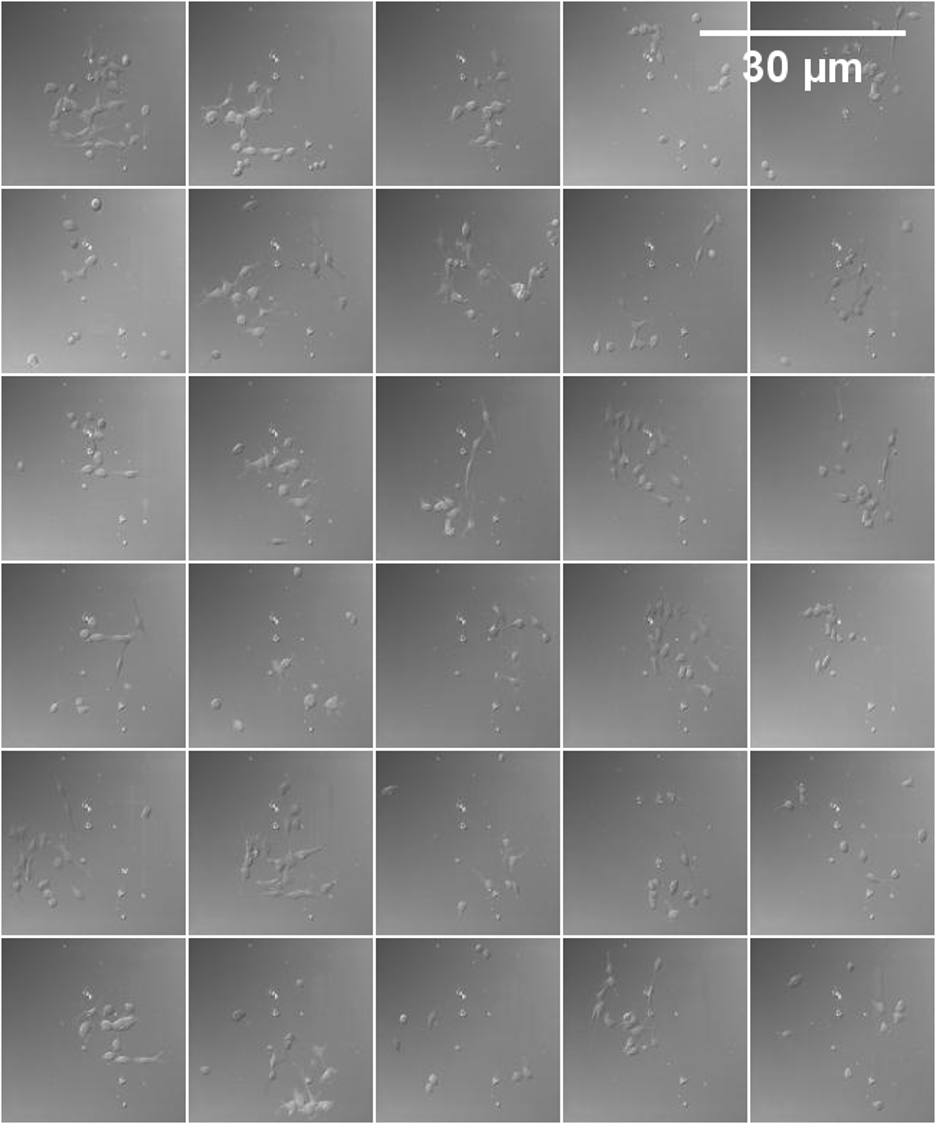

Refer to caption

Figure S9: MCO real images on CAR-T/NK, Neural, and Kaggle datasets; the first two rows represent the MCO images and their masks from the CAR-T/NK dataset. The third and fourth rows represent the MCO images and their masks from the Neural dataset. The fifth and sixth rows represent the MCO images and their masks from the Kaggle dataset.

Figure S10: MCO image generation on CAR-T/NK, Neural, and Kaggle datasets; the first two rows represent the MCO images and their masks from the CAR-T/NK dataset. The third and fourth rows represent the MCO images and their masks from the Neural dataset. The fifth and sixth rows represent the MCO images and their masks from the Kaggle dataset.

Figure S13: A sample of the final images created from the proposed method (128×\times128 for each sample) using the Neural dataset.

Figure S14: A sample of the final images created from the real images (128×\times128 for each sample) using the Neural dataset.